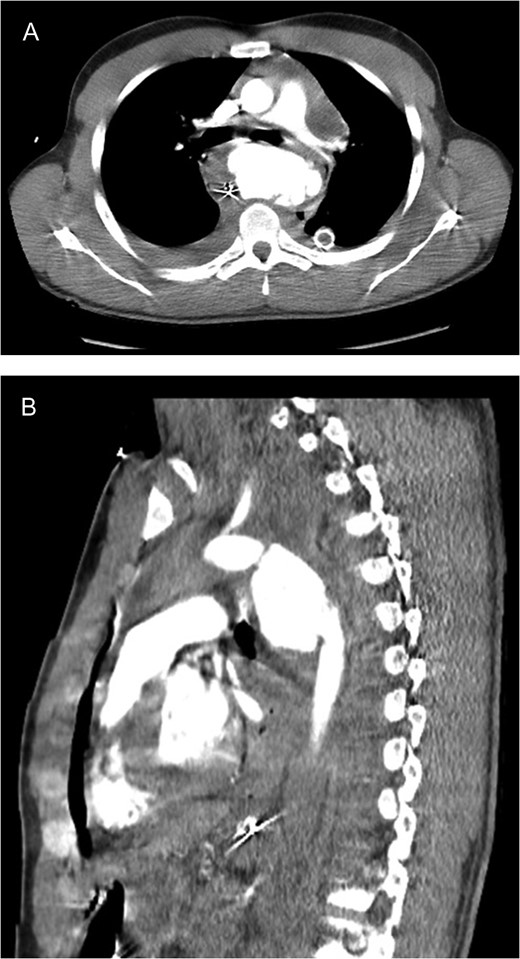

CXR following chest closure on postop day 3 demonstrated the aortic stent, multiple life support lines and bilateral lung opacification from the severe persistent respiratory failure.

He slowly improved and by postop day 11, the ECMO cannulas were discontinued. He later developed a pericardial effusion which required open drainage (postop day 18); however, the respiratory and renal failure eventually resolved. He later required surgery on his left hand fracture and subsequent debridement of the left groin. He was transferred to inpatient rehab on hospital day 35 and was discharged home by hospital day 44 without gross neurologic sequela.